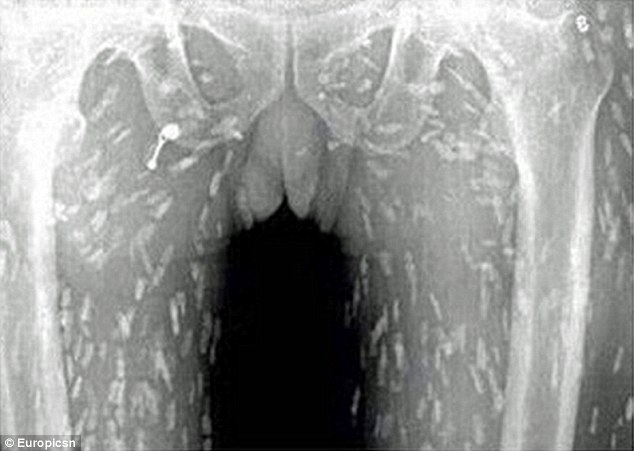

Τα σκουλήκια κυριολεκτικά κατέλαβαν το σώμα του. Όταν είδε τις ακτινογραφίες του, του κόπηκαν τα πόδια..

Όταν είδε τις ακτινογραφίες του, του κόπηκαν τα πόδια.. Σκουλήκια του έτρωγαν τα σωθικά και ο λόγος κάτι που πολλοί από εμάς τρώμε κάποιες φορές! – Εικόνα4 Μία μόλυνση από σκουλήκια-ταινίες μπορεί να οδηγήσει σε κυστικέρκωση. Αυτό συμβαίνει όταν τα σκουλήκια καταφέρνουν να μπουν στην κυκλοφορία του αίματος! Μετά μπορούν να πάνε στον εγκέφαλο, με κίνδυνο της ίδιας της ζωής του ασθενή.